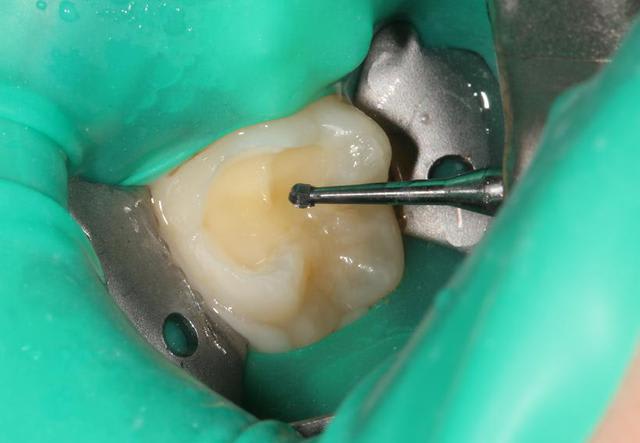

P1020718_nq7p7t.jpg

Voir le message contenant cette image